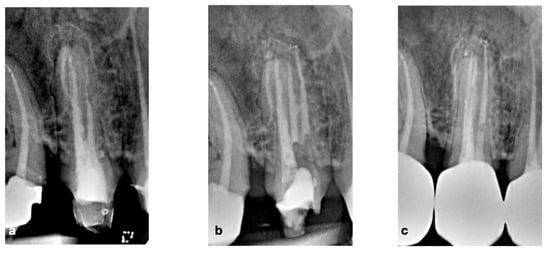

2.1. CASE 1

2.2. CASE 2

2.3. CASE 3

2.4. CASE 4

2.5. CASE 5